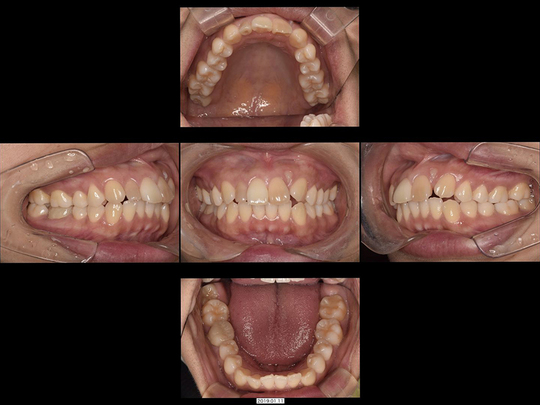

矯正前

画像をクリックで拡大

矯正後

治療の説明

抜歯後、「入れ歯が嫌なら歯を削ってブリッジがインプラントにするしかない」と診断されたケースです。

精査の結果、CT画像上においても、インプラント治療は非常に困難で、ブリッジ治療を選択すると両サイドの歯の削る量が大きすぎるため、事前に神経を抜かないと対応が困難であることが判明しました。20代前半という年齢も考慮し、高齢者になってもメインテナンスしやすいのは、すべて自分の歯だけであることを考慮して、矯正治療を選択されました。表側の矯正装置にて上下の歯並び・咬み合わせを整えました。

治療の期間・回数

18か月、20回

​費用

985,600円